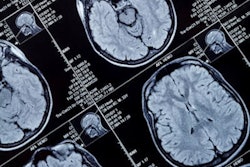

ACR CRI will serve as the operations center as announced on August 1 at the Alzheimer's Association International Conference 2022. ACR CRI will provide guidance, education, and best practices in imaging care for patients with dementia and Alzheimer's. Imaging plays a crucial role in diagnosing and monitoring patients with dementia and Alzheimer's.

Clinical dementia care sites will participate in ALZ-NET. Imaging facilities will report to treating physicians.